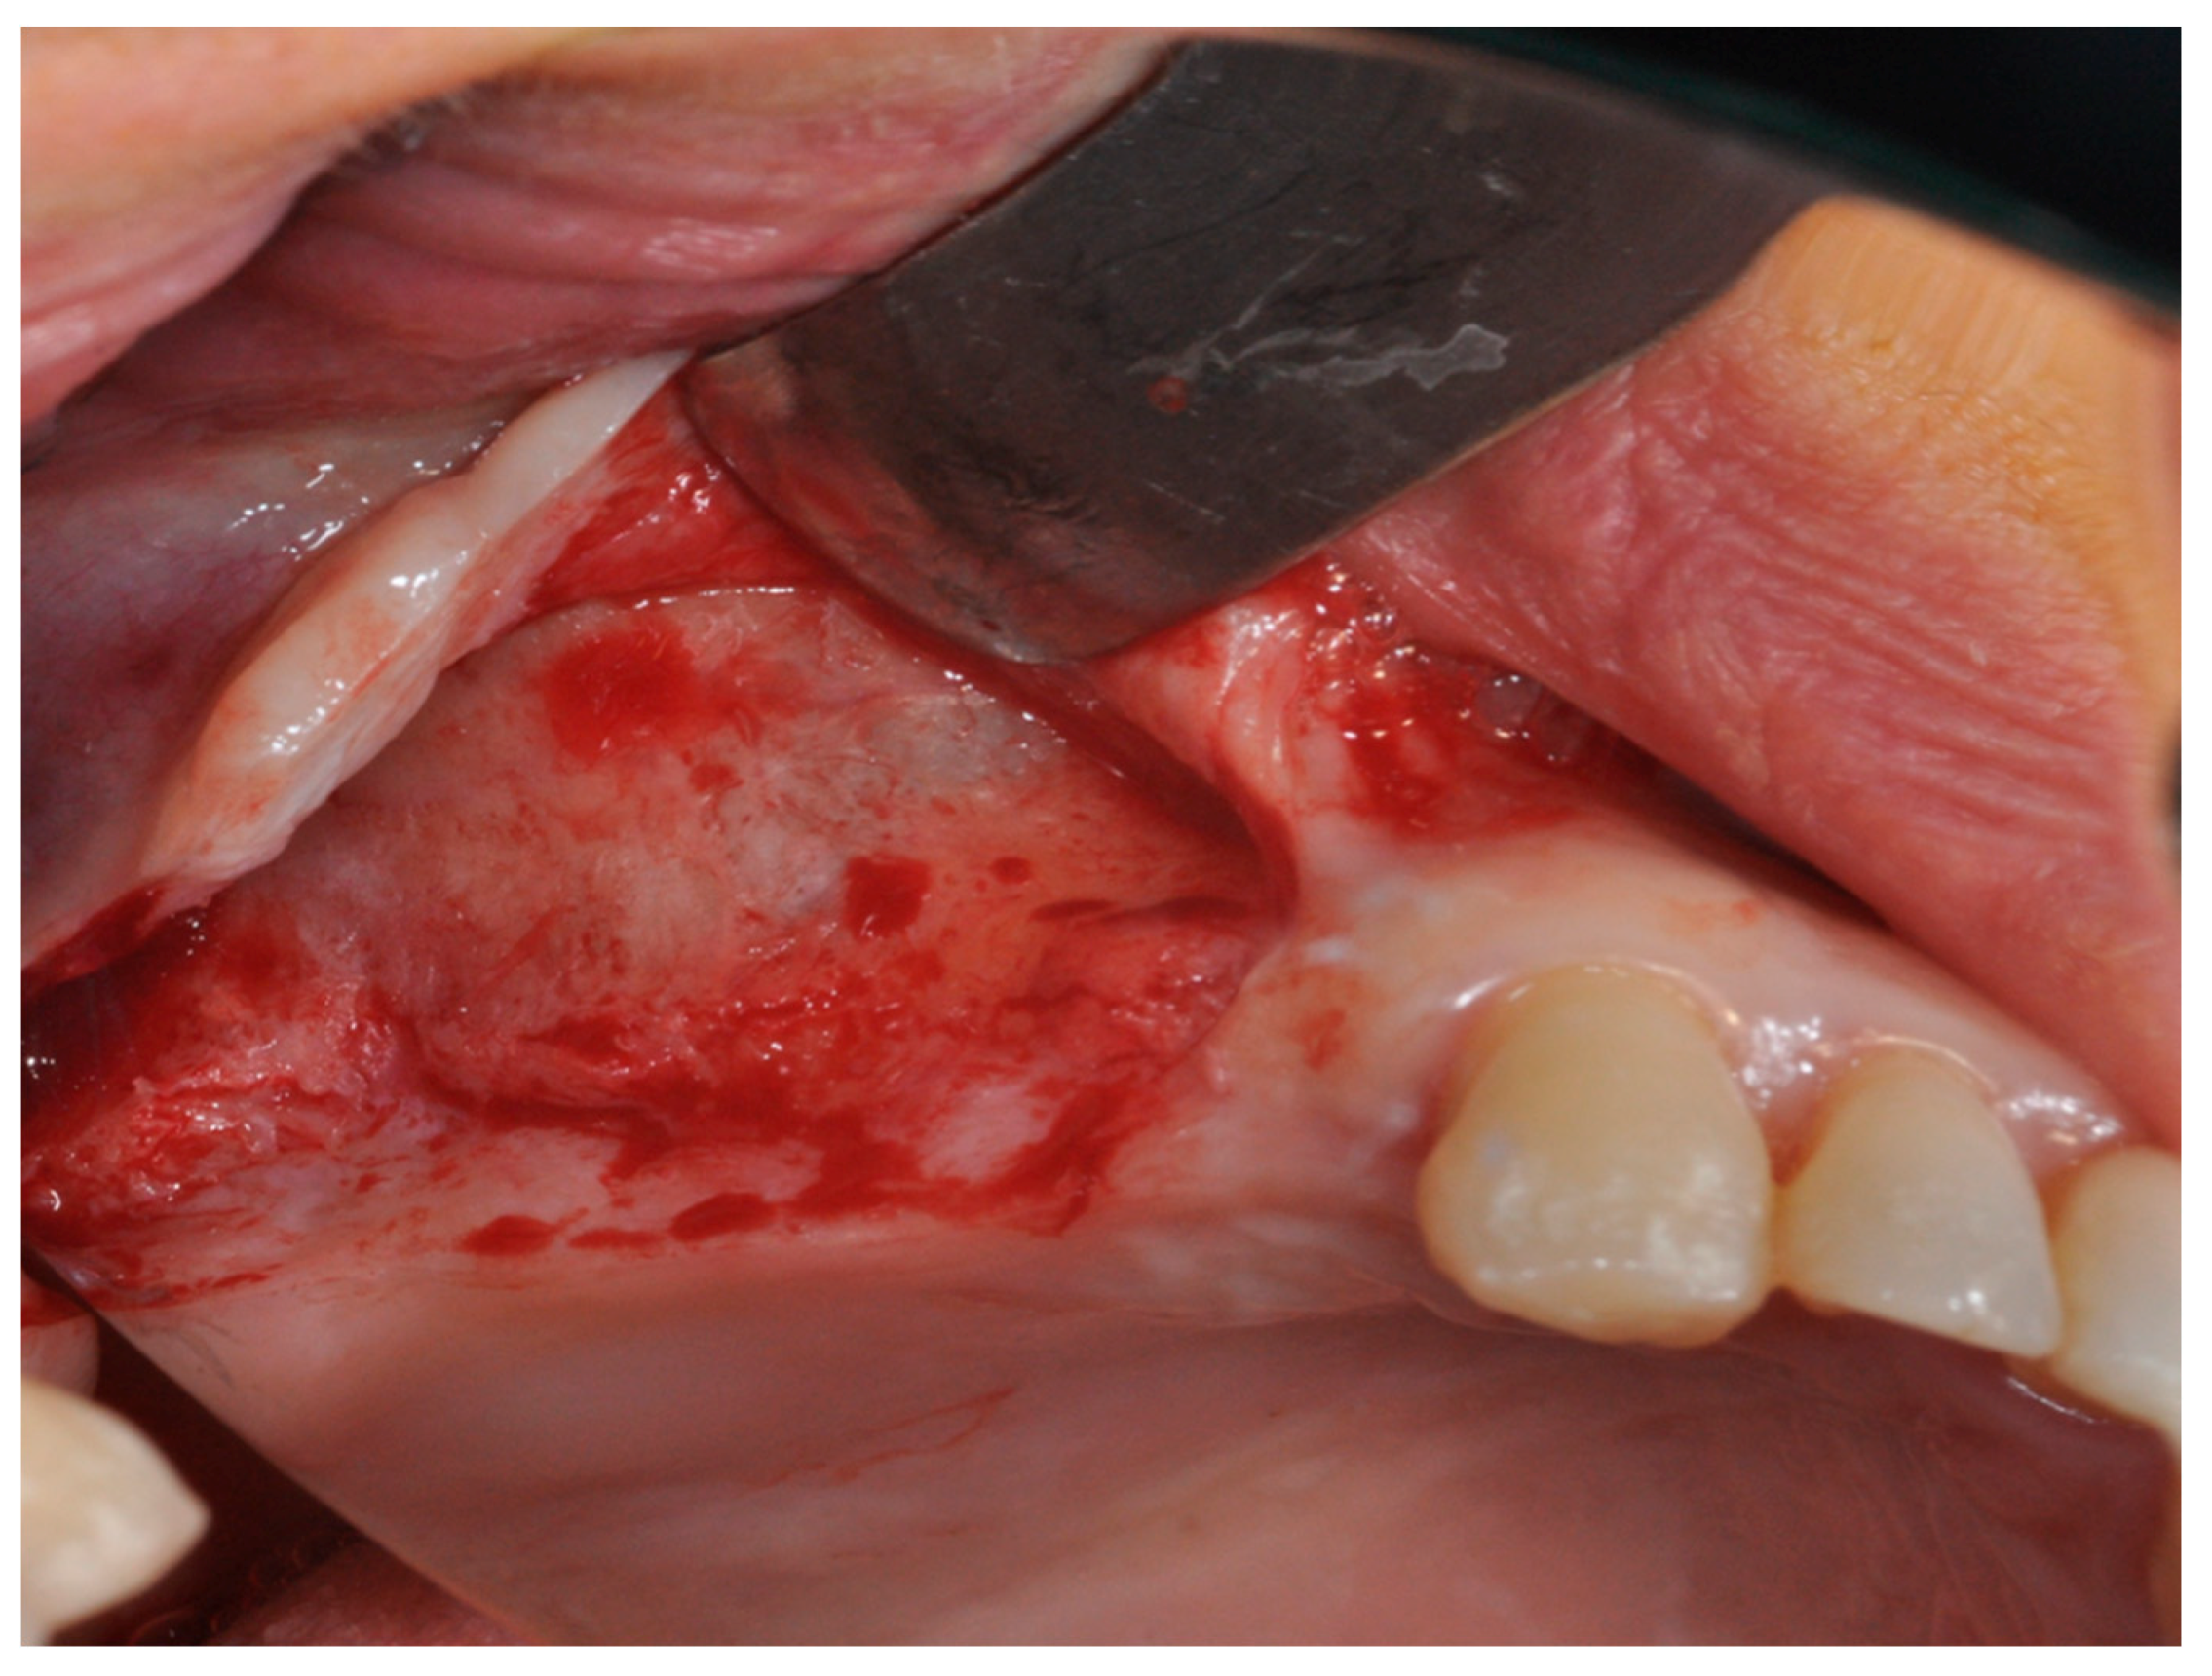

2.1. Group I

2.2. Group II

4. Materials and Methods